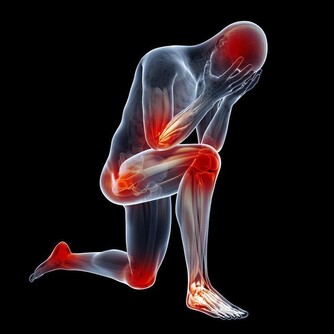

冠心病是冠狀動脈性心髒病的簡稱,是一種由于冠狀動脈固定性(動脈粥樣硬化)或動力性(血管痙攣)狹窄或阻塞,發生冠脈循環障礙,引起心肌氧供需之間失衡而導致心肌缺血缺氧或壞死的一種心臟病。

經過勞累、情緒激動、飽食、寒冷等情況下發生的心前區或胸骨後悶脹、疼痛,每次持續數分鐘,提示很可能是心絞痛。當心絞痛發作時,由於心肌缺血,可發生各種心律失常,常伴有心悸、脈搏間歇等表現。

心肌梗死是由冠狀動脈分支血管斑塊突然破裂導致的急性閉塞所致,常伴有長時間(一般超過30分鐘)的胸悶、胸痛等症狀,有的還會出現上腹疼痛、噁心、嘔吐等,嚴重者可發生心室纖顫,出現意識喪失、抽搐,甚至死亡。